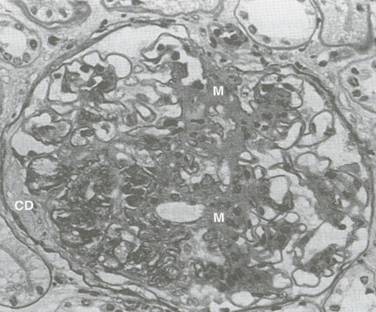

b). Leziunile difuze glomerulare (Bell si Fahr) par sa fie cele mai obisnuite leziuni din ND (Figura 5.11). Are loc acumularea de material PAS pozitiv in peretii capilarelor glomerulare, care devin mai grosi. Principala modificare o constituie ingrosarea membranei bazale, care poate atinge 5000-8000 . Ele apar prin cresterea ariei mezangiale si ingrosarea peretelui capilar, cu extinderea matricei mezangiale, incluzand capilarele. In stadiile initiale este dificil de a distinge expansiunea mezangiala minora de modificarile care apar odata cu imbatranirea sau alta patologie glomerulara. In cazuri mai severe, peretele capilar ingrosat si expansiunea mezangiala conduc la ingustare capilara si eventual hialinizare completa. Fibroza periglomerulara este adeseori prezenta in stadiile avansate. Aceste leziuni nu sunt specifice, ele mai apar si la persoanele fara diabet: varstnici, hipertensivi.

Figura 5.11. Leziuni difuze glomerulare si exudative (microscopie optica)